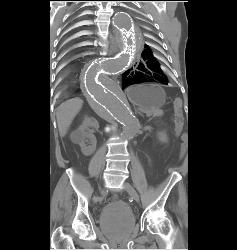

Left Iliac Artery Disease